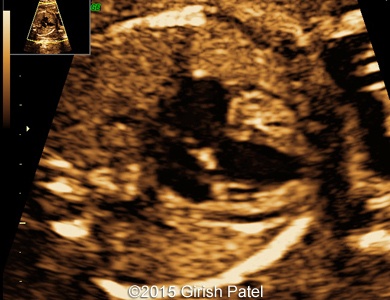

Following images and videos show a case of double inlet left ventricle with transposition of the great arteries that was seen at 26 and 36 weeks of otherwise non-complicated pregnancy.

Images 1, 2, 3, and 4: 2D images showing transverse scan of the heart with double inlet left ventricle and transposition of the great arteries. Following structures can be seen: dominant enlarged left ventricle (LV); diminutive right ventricle (RV) connected to the left ventricle via small bulboventricular foramen; both, left atrium (LA), and right atrium (RA) open to the left ventricle via separate tricuspid and mitral valves; foramen ovale flap can be seen within the left atrium; enlarged pulmonary artery (PA) arises from the left ventricle; small part of the aorta (Ao) arising from the diminutive right ventricle can be also seen.

Images 8, 9, 10: 2D gray scale and color Doppler images showing the heart with double inlet left ventricle and transposition of the great arteries - the images 8 and 9 show mitral and tricuspid valves opened to the left ventricle. The image 10 shows branching of the pulmonary artery (RPA, LPA), arising from the dominant left ventricle.